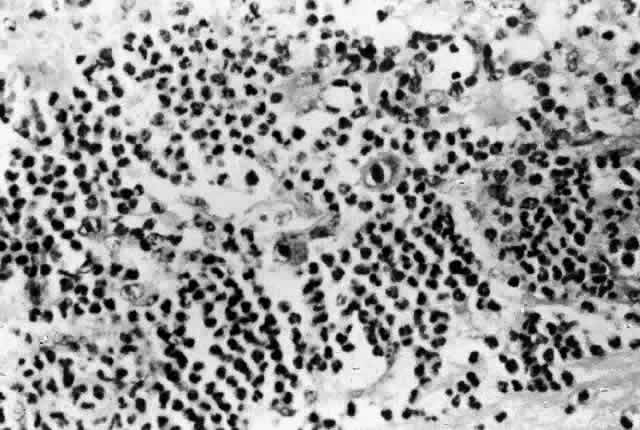

Histologic studies of AIDS-related CMV retinopathy demonstrate the tissue necrosis and cytomegalic cells characteristic of all CMV infections (Fig. 1).9,17 Electron-microscopic and immunochemical studies have identified CMV viral particles and antigen in a patchy distribution throughout all layers of the retina and occasionally in contiguous retinal pigment epithelial cells.9 Viral antigens are only rarely identified in the choroid.9,18 Viral antigen in the choroid has been found in association with vessels and is not always adjacent to areas of retinopathy, suggesting that the virus reaches the choroid through independent hematogenous spread rather than by extension of infection from the retina.

Fig. 1. CMV retinopathy, with neutrophilic infiltration in an area of necrotic retina. Cytomegalic cells with intranuclear inclusions are present in the center of the field (hematoxylin-eosin; original magnification × 600). (Printed with permission from Pepose JS, Holland GN, Nestor MS et al: Acquired immune deficiency syndrome: Pathogenic mechanisms of ocular disease. Ophthalmology 92:472, 1985)

Among cases of AIDS examined at autopsy, 22% to 50% of those with CMV retinopathy have neutrophilic infiltrates in retinal tissue.9,19 This finding is atypical when compared with CMV retinopathy in non-AIDS patients, in which only a sparse lymphocytic infiltrate is observed. The difference has been attributed to intact granulocyte function and chemotaxis in patients with AIDS, in contrast to infants, organ transplant recipients, and patients with malignancies who can have more severe quantitative or qualitative granulocyte dysfunction.9 It has been noted that patients on immunosuppressive drugs can develop marked inflammatory reactions to CMV retinopathy when such drugs are withdrawn.14 Acute inflammatory cells may extend into the adjacent choroid despite the absence of identifiable viral antigens.9 The vitreous usually remains remarkably free of inflammatory material, despite the presence of virus in the vitreous cavity.20